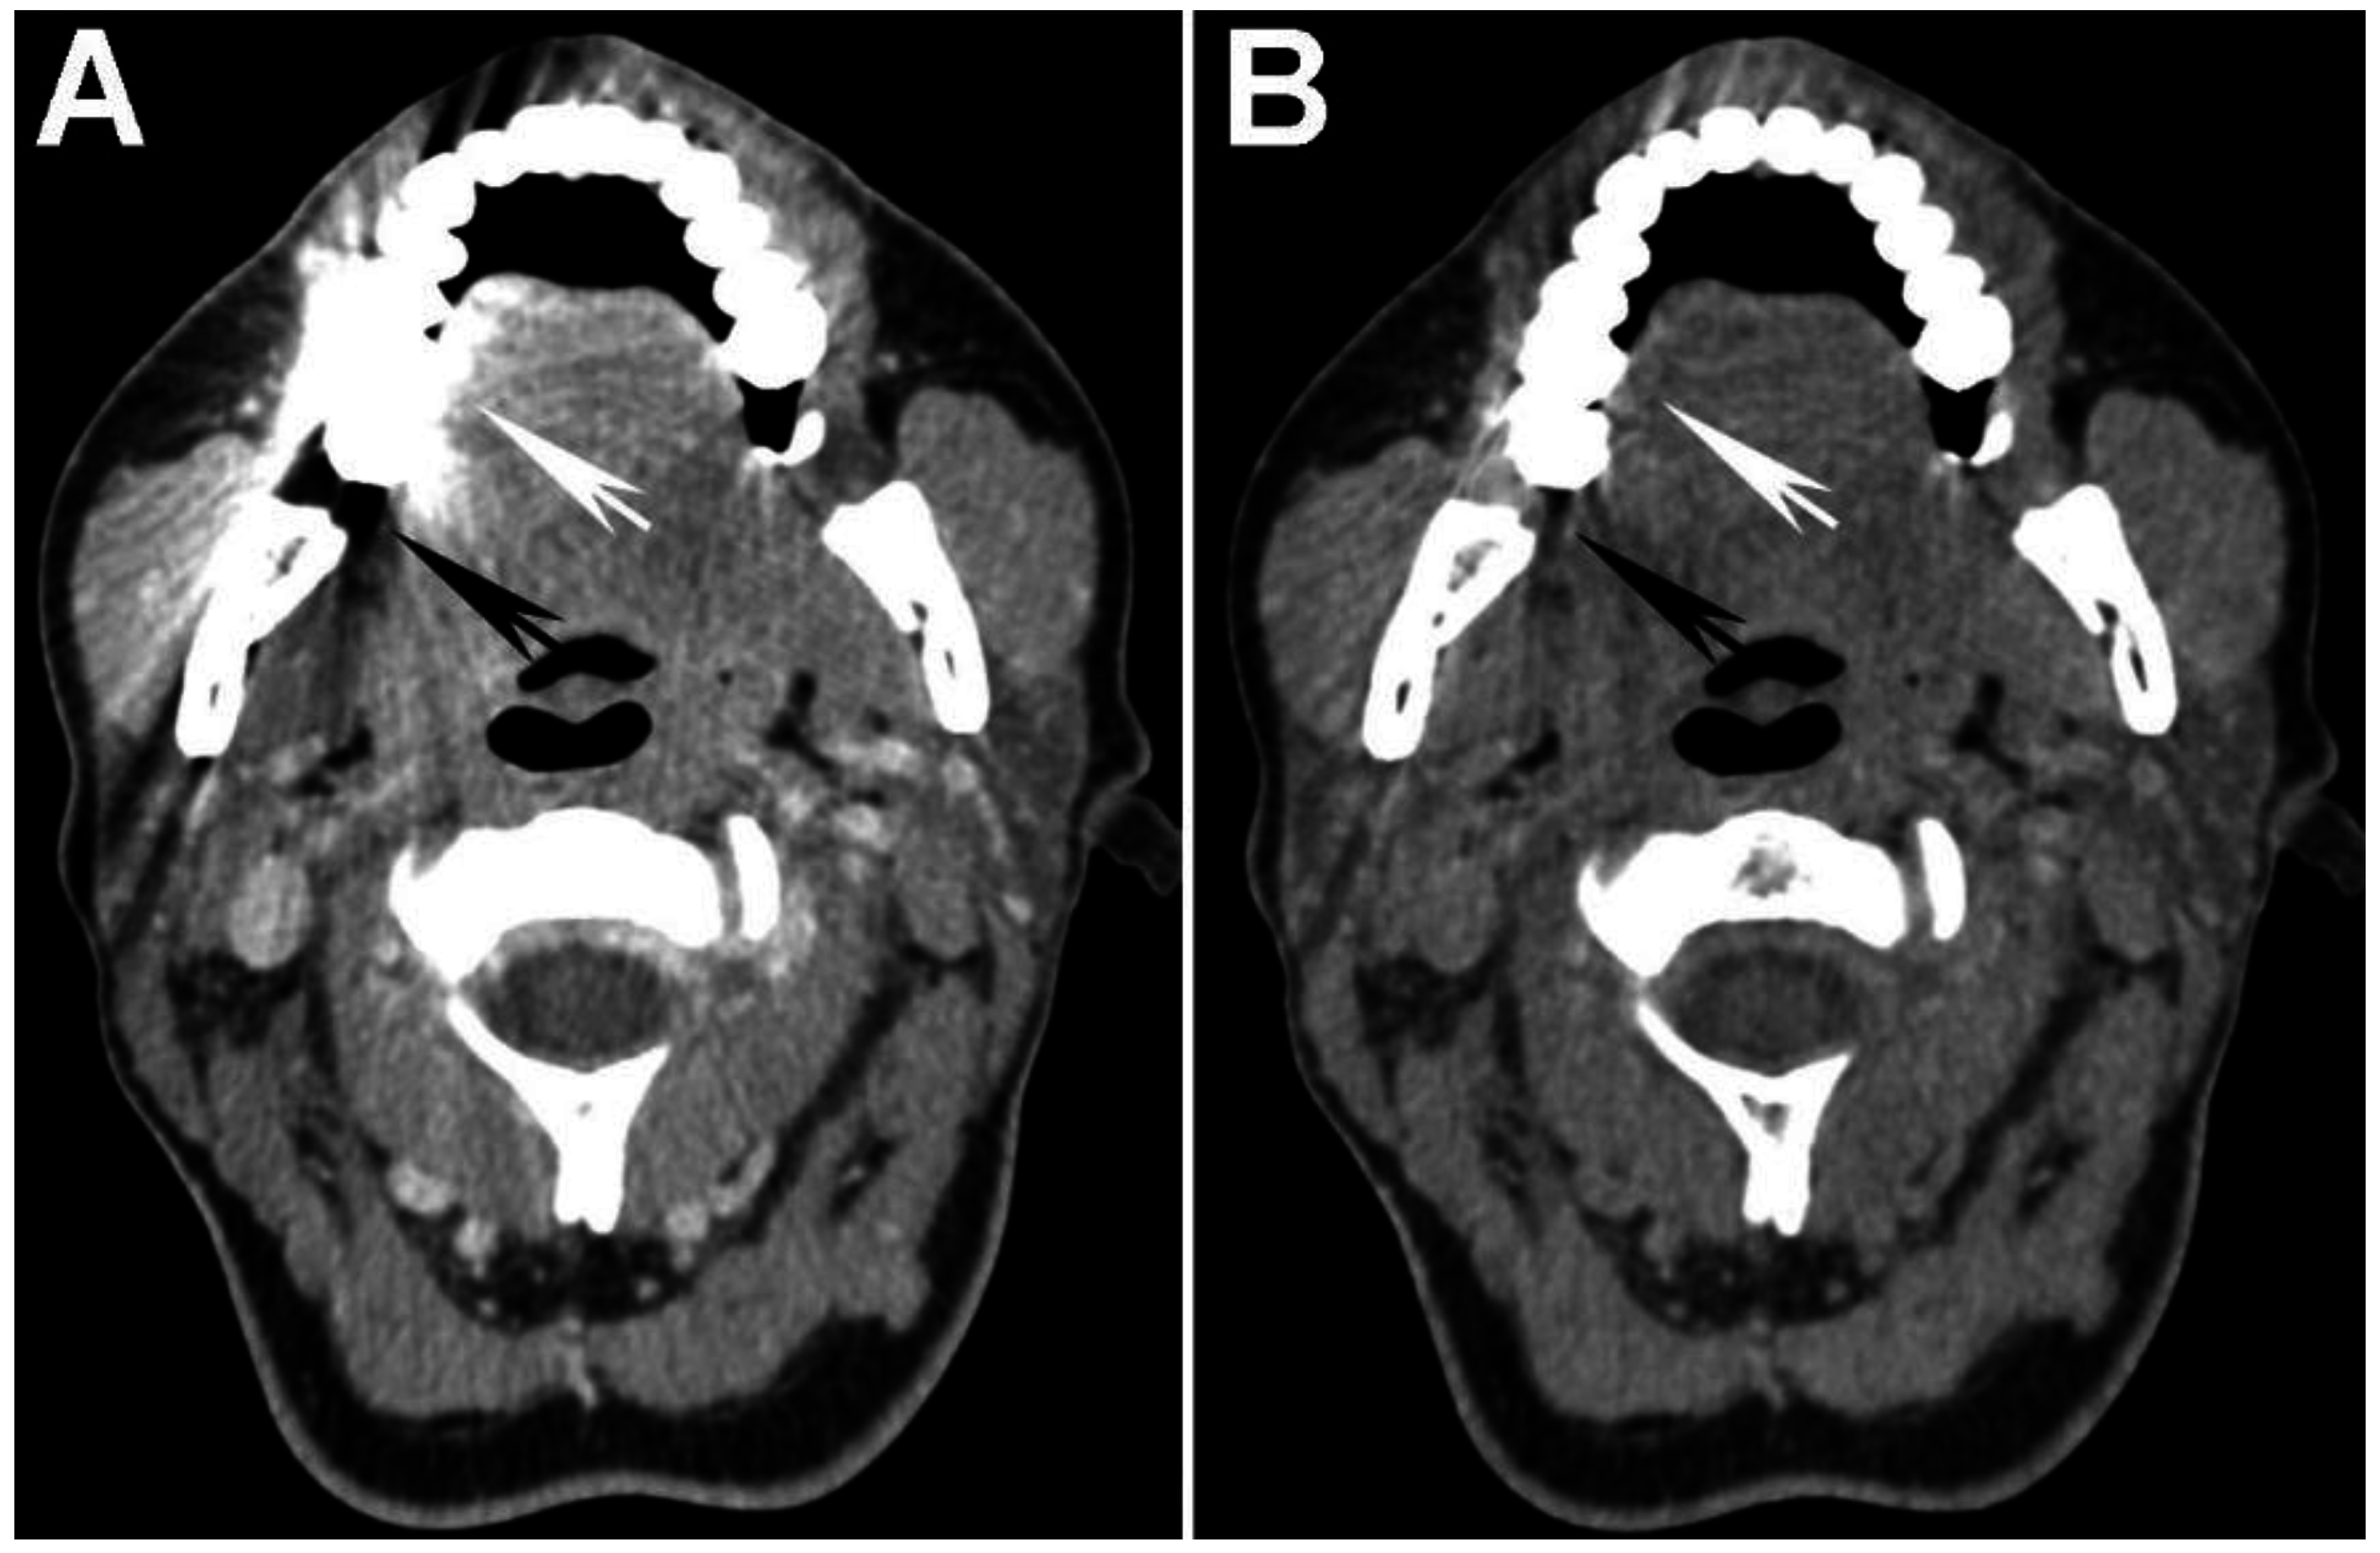

The increased attenuation of iodine at lower energies can be taken advantage of in order to increase the visual conspicuity and measured attenuation/density of tumor using DECT. In a study performed using a single-source DECT scanner with fast kVp switching, Lam et al. [17] evaluated optimal VMI reconstructions for assessment of normal anatomy and HNSCC. The authors concluded through objective analysis of signal-to-noise ratio (SNR) that 65 keV VMIs had the best overall image quality and suggested that it should be used as the default reconstruction for assessment of the neck. The optimal, highest SNR at 65 keV was closely followed by the 70 keV VMIs, the typical default reconstruction believed to most closely resemble the standard 120-kVp SECT acquisition, based on data extrapolated from body imaging [41,42]. In the same study, it was also shown that tumor conspicuity/attenuation is highest on 40 keV VMIs [17] (Figure 2 and Figure 3). Furthermore, it was shown that the attenuation difference between tumor and muscles was also highest on the 40 keV VMIs, despite the higher image noise on these reconstructions [17] (Figure 2 and Figure 3). We have recently expanded on these observations using data obtained at our two different institutions and also demonstrated that subjectively, 40 keV is the preferred VMI for targeted tumor evaluation by both general radiologists and those who specialize in head and neck imaging [43].

Figure 2. Increased tumor attenuation on 40 keV virtual monochromatic images (VMIs). (A) 70 keV single energy equivalent CT image of a right base of tongue tumor (large black arrow) and pathologic right level IIA lymph node (small white arrow) is shown. Note the similar density of both lesions compared to the normal right sternocleidomastoid muscle (M); (B) On the 40 keV image displayed using the same window-level settings, note the higher lesion density as well as higher relative contrast compared to muscle (M). Also note the increased image noise on the 40 keV VMI (B) compared to 70 keV VMI (A).